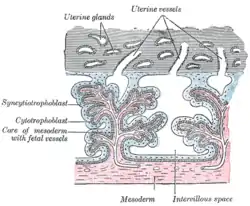

- Floating villi float freely in the intervillous space. They exhibit a bi-layered epithelium consisting of cytotrophoblasts with overlaying syncytium (syncytiotrophoblast).

| Secondary | The villi increase in size and ramify, while the mesoderm grows into them. | 16–21 days | trophoblast and mesoderm[1] |

| Tertiary | Branches of the umbilical artery and umbilical vein grow into the mesoderm, and in this way the chorionic villi are vascularized. | 17–22 days | trophoblast, mesoderm, and blood vessels[1] |

The bulk of the villi consist of connective tissues that contain blood vessels. Most of the cells in the connective tissue core of the villi are fibroblasts. Macrophages known as Hofbauer cells are also present.